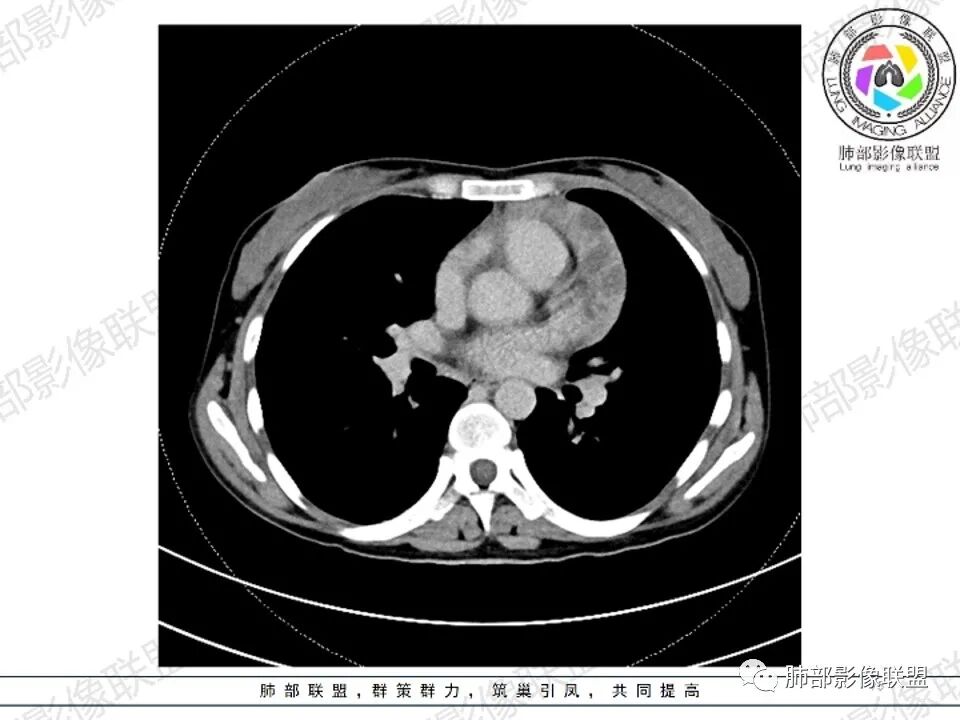

女,27,间断头晕、乏力3年,左眼视物模糊2月。贫血。胸部CT:前纵隔不规则肿块,多结节融合,边界不清,沿主动脉及肺动脉间隙生长,平扫密度欠均匀,增强扫描可见多发低密度坏死,纵隔血管供血穿行,腋窝多发大小不等淋巴结肿大。考虑恶性病变,胸腺癌?肉瘤?淋巴瘤?鉴别胸腺瘤、结节病等。

2.影像显示前纵隔不规则块状影,依势贴附心脏大血管旁,密度不均,边界不甚清楚,有结节融合感。

3.病灶轻度不均匀强化,可见血管穿行,散在液性低密度区。

双肺门未见肿大淋巴结。

4.双侧腋窝区见增大淋巴结,边界清楚。

1.年轻女性,前纵隔不规则块状影,密度不均,边界不甚清楚,有结节融合感,轻度不均匀强化,可见血管穿行,最常见最符合的无疑是淋巴瘤!